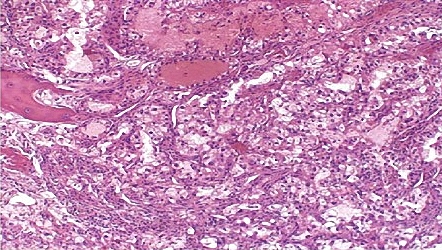

Renal cell carcinoma